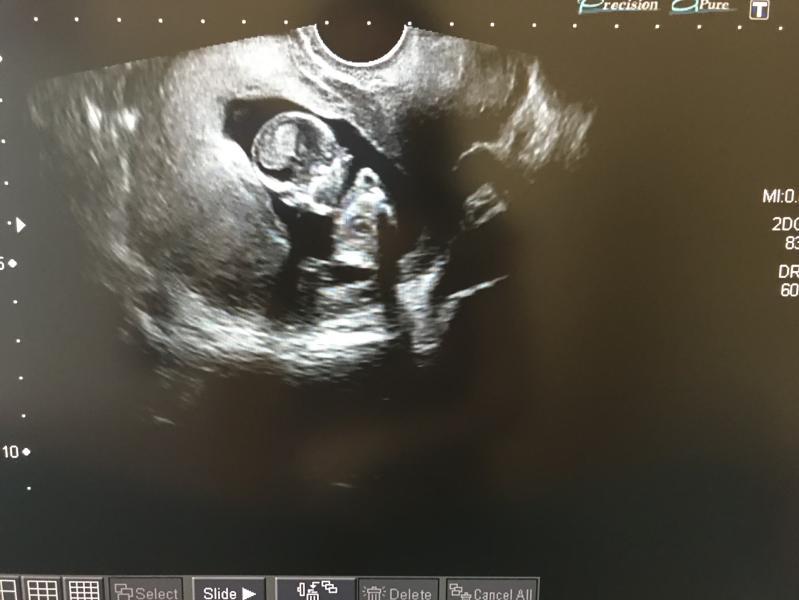

Ура! У нас есть первое фото.☺️Сегодня первый раз увидела своего малыша, эмоции не передаваемые 😌